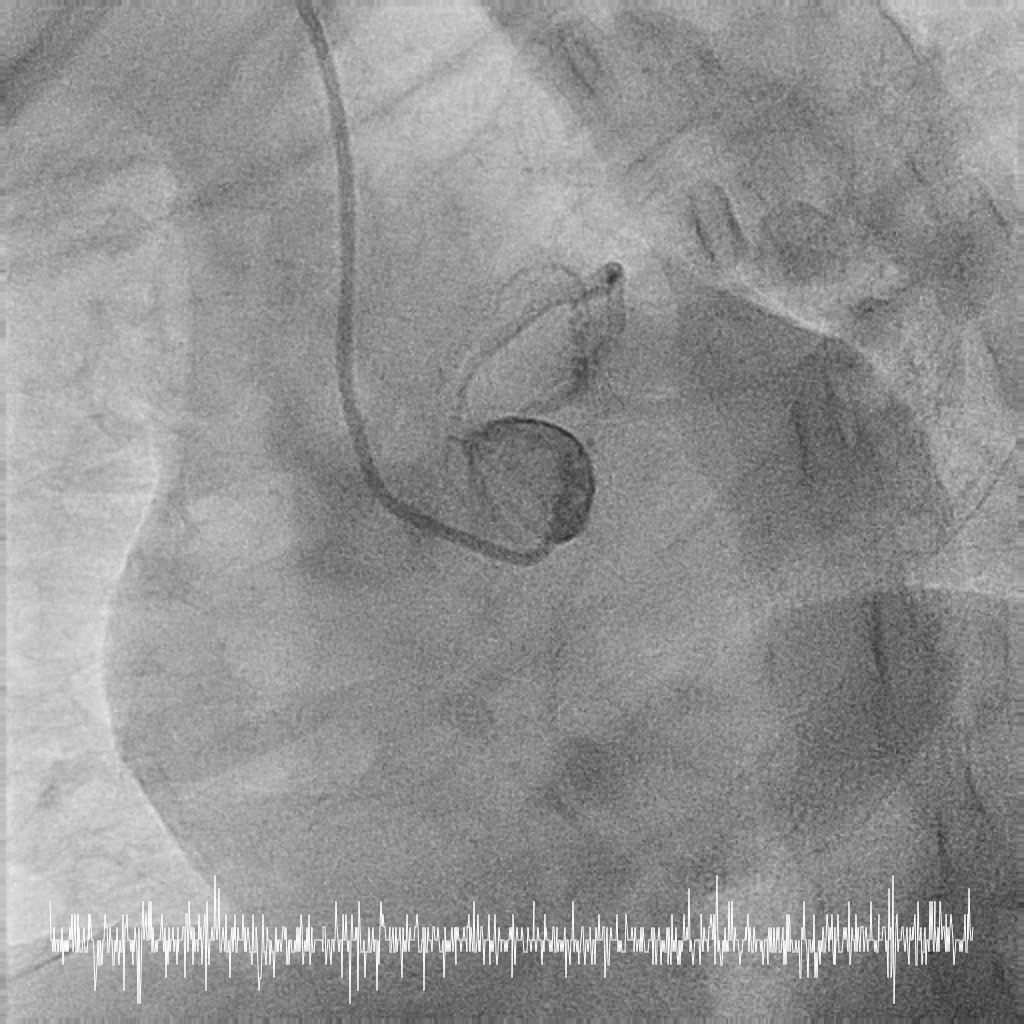

Femoral approach was chosen with a 7F sheath. A 7F JL4 guiding catheter was used for better support. JL4 was not coaxially engaged but positioned close to the ostial LM. Sion Blue ES was wired into LAD from the aortic cusp. A BMW wire was wired into LCx to provide additional support and as a safety wire in case of plaque shift into ostial LCx. Ostial LM was predilated with 3.0/10mm NC balloon at 12ATM which was delivered via Sion Blue ES with the guide and wire floating in the aorta. IVUS after predilatation revealed an ostial LM MLA 5.28mm2 with vessel size 4.0mm. Proximal LAD measured 3.0mm in size and exhibited fibrotic plaque with 70% plaque burden. Both ostial LM and proximal LAD were predilated with 3.0/15mm NC balloon delivered using the floating guide and Sion Blue ES. A 3.0/33mm DES was delivered and deployed with similar technique into proximal LAD using multiple projections for precise positioning to ensure proximal stent edge protrusion of 1-2mm into the aorta. POT of LM and ostial flare were performed using 3.75/15mm NC balloon. Proximal LAD was postdilated with 3.0/15mm NC balloon. IVUS confirmed a well-opposed stent without stent edge dissection. The final ostial LM MSA was 9.7mm2, with stent protrusion (1.7mm) into the aorta (less than one quadrant). The entire ostial LM was covered with stent struts.